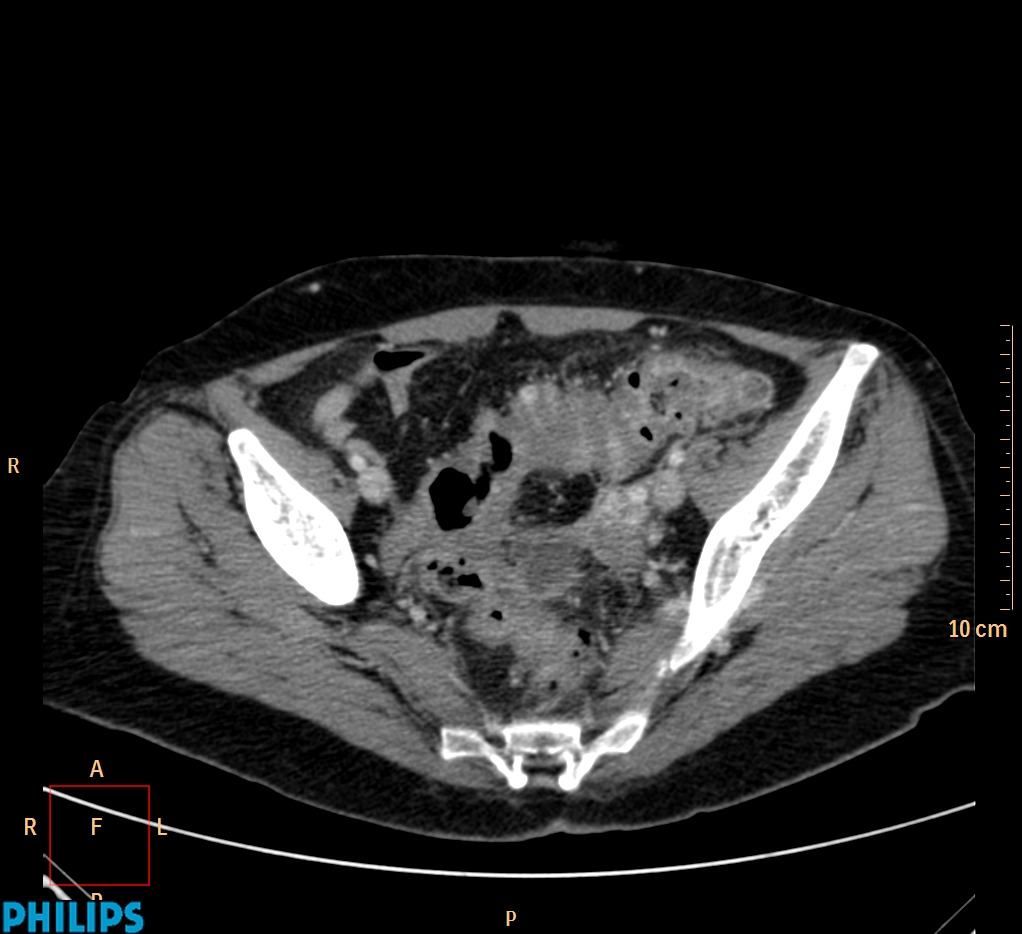

ΕΚΚΟΛΠΩΜΑΤΑ ΠΑΧΕΟΣ ΕΝΤΕΡΟΥ Posted by ΙΠΠΟΚΡΑΤΕΙΟ ΙΩΑΝΝΙΝΩΝ | Dec 16, 2020 | ΠΕΠΤΙΚΟ | 0 ΚΛΙΝΙΚΑ ΣΤΟΙΧΕΙΑ – ΙΣΤΟΡΙΚΟ υποτροπιάζοντες επαναλαμβανόμενοι πυρετοί κυρίως απογευματινές ώρες ΕΡΓΑΣΤΗΡΙΑΚΟΣ ΕΛΕΓΧΟΣ ΑΠΕΙΚΟΝΙΣΤΙΚΟΣ ΕΛΕΓΧΟΣ διακρίνονται τα αποστήματα στην ελάσσονα πύελο, καθώς και εκκολπώματα με εικόνα πάχυνσης του τοιχώματος του σιγμοειδούς ΣΥΖΗΤΗΣΗ